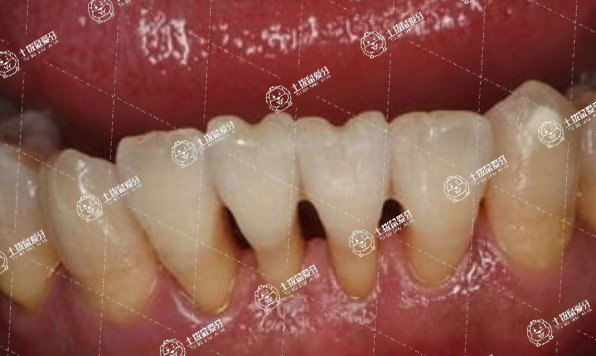

矯正牙齒牙齦腫了是怎么回事

牙齒矯正導(dǎo)致牙齦腫痛可能是正常的生理現(xiàn)象,也可能是病理性因素所致,一般需要根據(jù)具體情況進(jìn)行具體分析。

2、病理性因素:牙齒矯正后,如果護(hù)理工作不到位,很可能會(huì)引起牙齦炎、牙周炎、根尖周炎等口腔疾病。